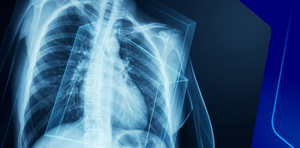

- Differentiate between different radiological modalities.

- Know the common terminology used in describing in different radiological modalities.